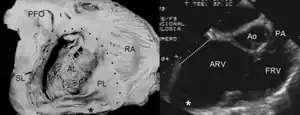

Pathological specimen and ultrasound image of a heart with Ebstein's anomaly: Abbreviations: RA: right atrium; ARV: atrialized right ventricle; FRV: functional right ventricle; AL: anterior leaflet; SL: septal leaflet; LA: left atrium; LV: left ventricle; asterisk: grade II tethering of the tricuspid septal leaflet

The annulus of the valve is still in the normal position. The valve leaflets, however, are to a varying degree, attached to the walls and septum of the right ventricle. A subsequent "atrialization" of a portion of the morphologic right ventricle (which is then contiguous with the right atrium) is seen. This causes the right atrium to be large and the anatomic right ventricle to be small in size.

Anatomic abnormalities

Typically, anatomic abnormalities of the tricuspid valve exist, with enlargement of the anterior leaflet of the valve. The other leaflets are described as being plastered to the endocardium. Tethering the underlying ventricular wall is the most common for the posterior and septal leaflets, and sail-like anterior leaflets may be tethered to the RV free wall also. About 50% of individuals with Ebstein's anomaly have an associated shunt between the right and left atria, either an atrial septal defect or a patent foramen ovale.[4]